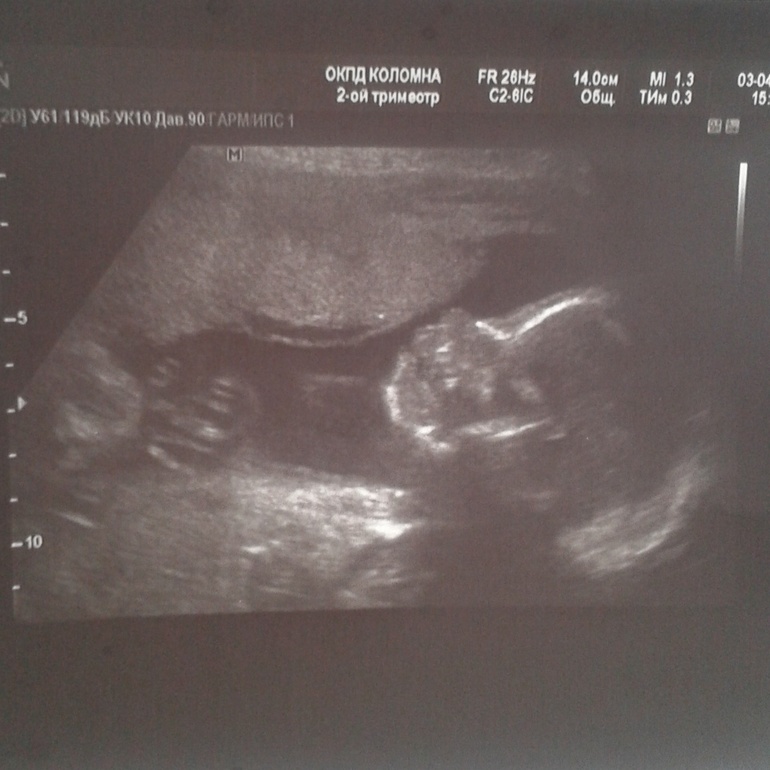

Была на УЗИ. Все просто замечательно. Девочка 100%, весит 530 грамм, развивается замечательно. Плацента высоко, рубец состоятельный. А вот внутри рядом с рубцом варикоз. Поэтому то и тянет у меня низ живота. Врач прописал пить флебодию. А еще велел прекратить принимать дюфастон, а на ночь 1 таблетку утрожестана вагинально. К чему бы это такие новшества? Сегодня сдала кровь и мочу, в пятницу пойду взвешиваться. Наверное, весы зашкалят)))))